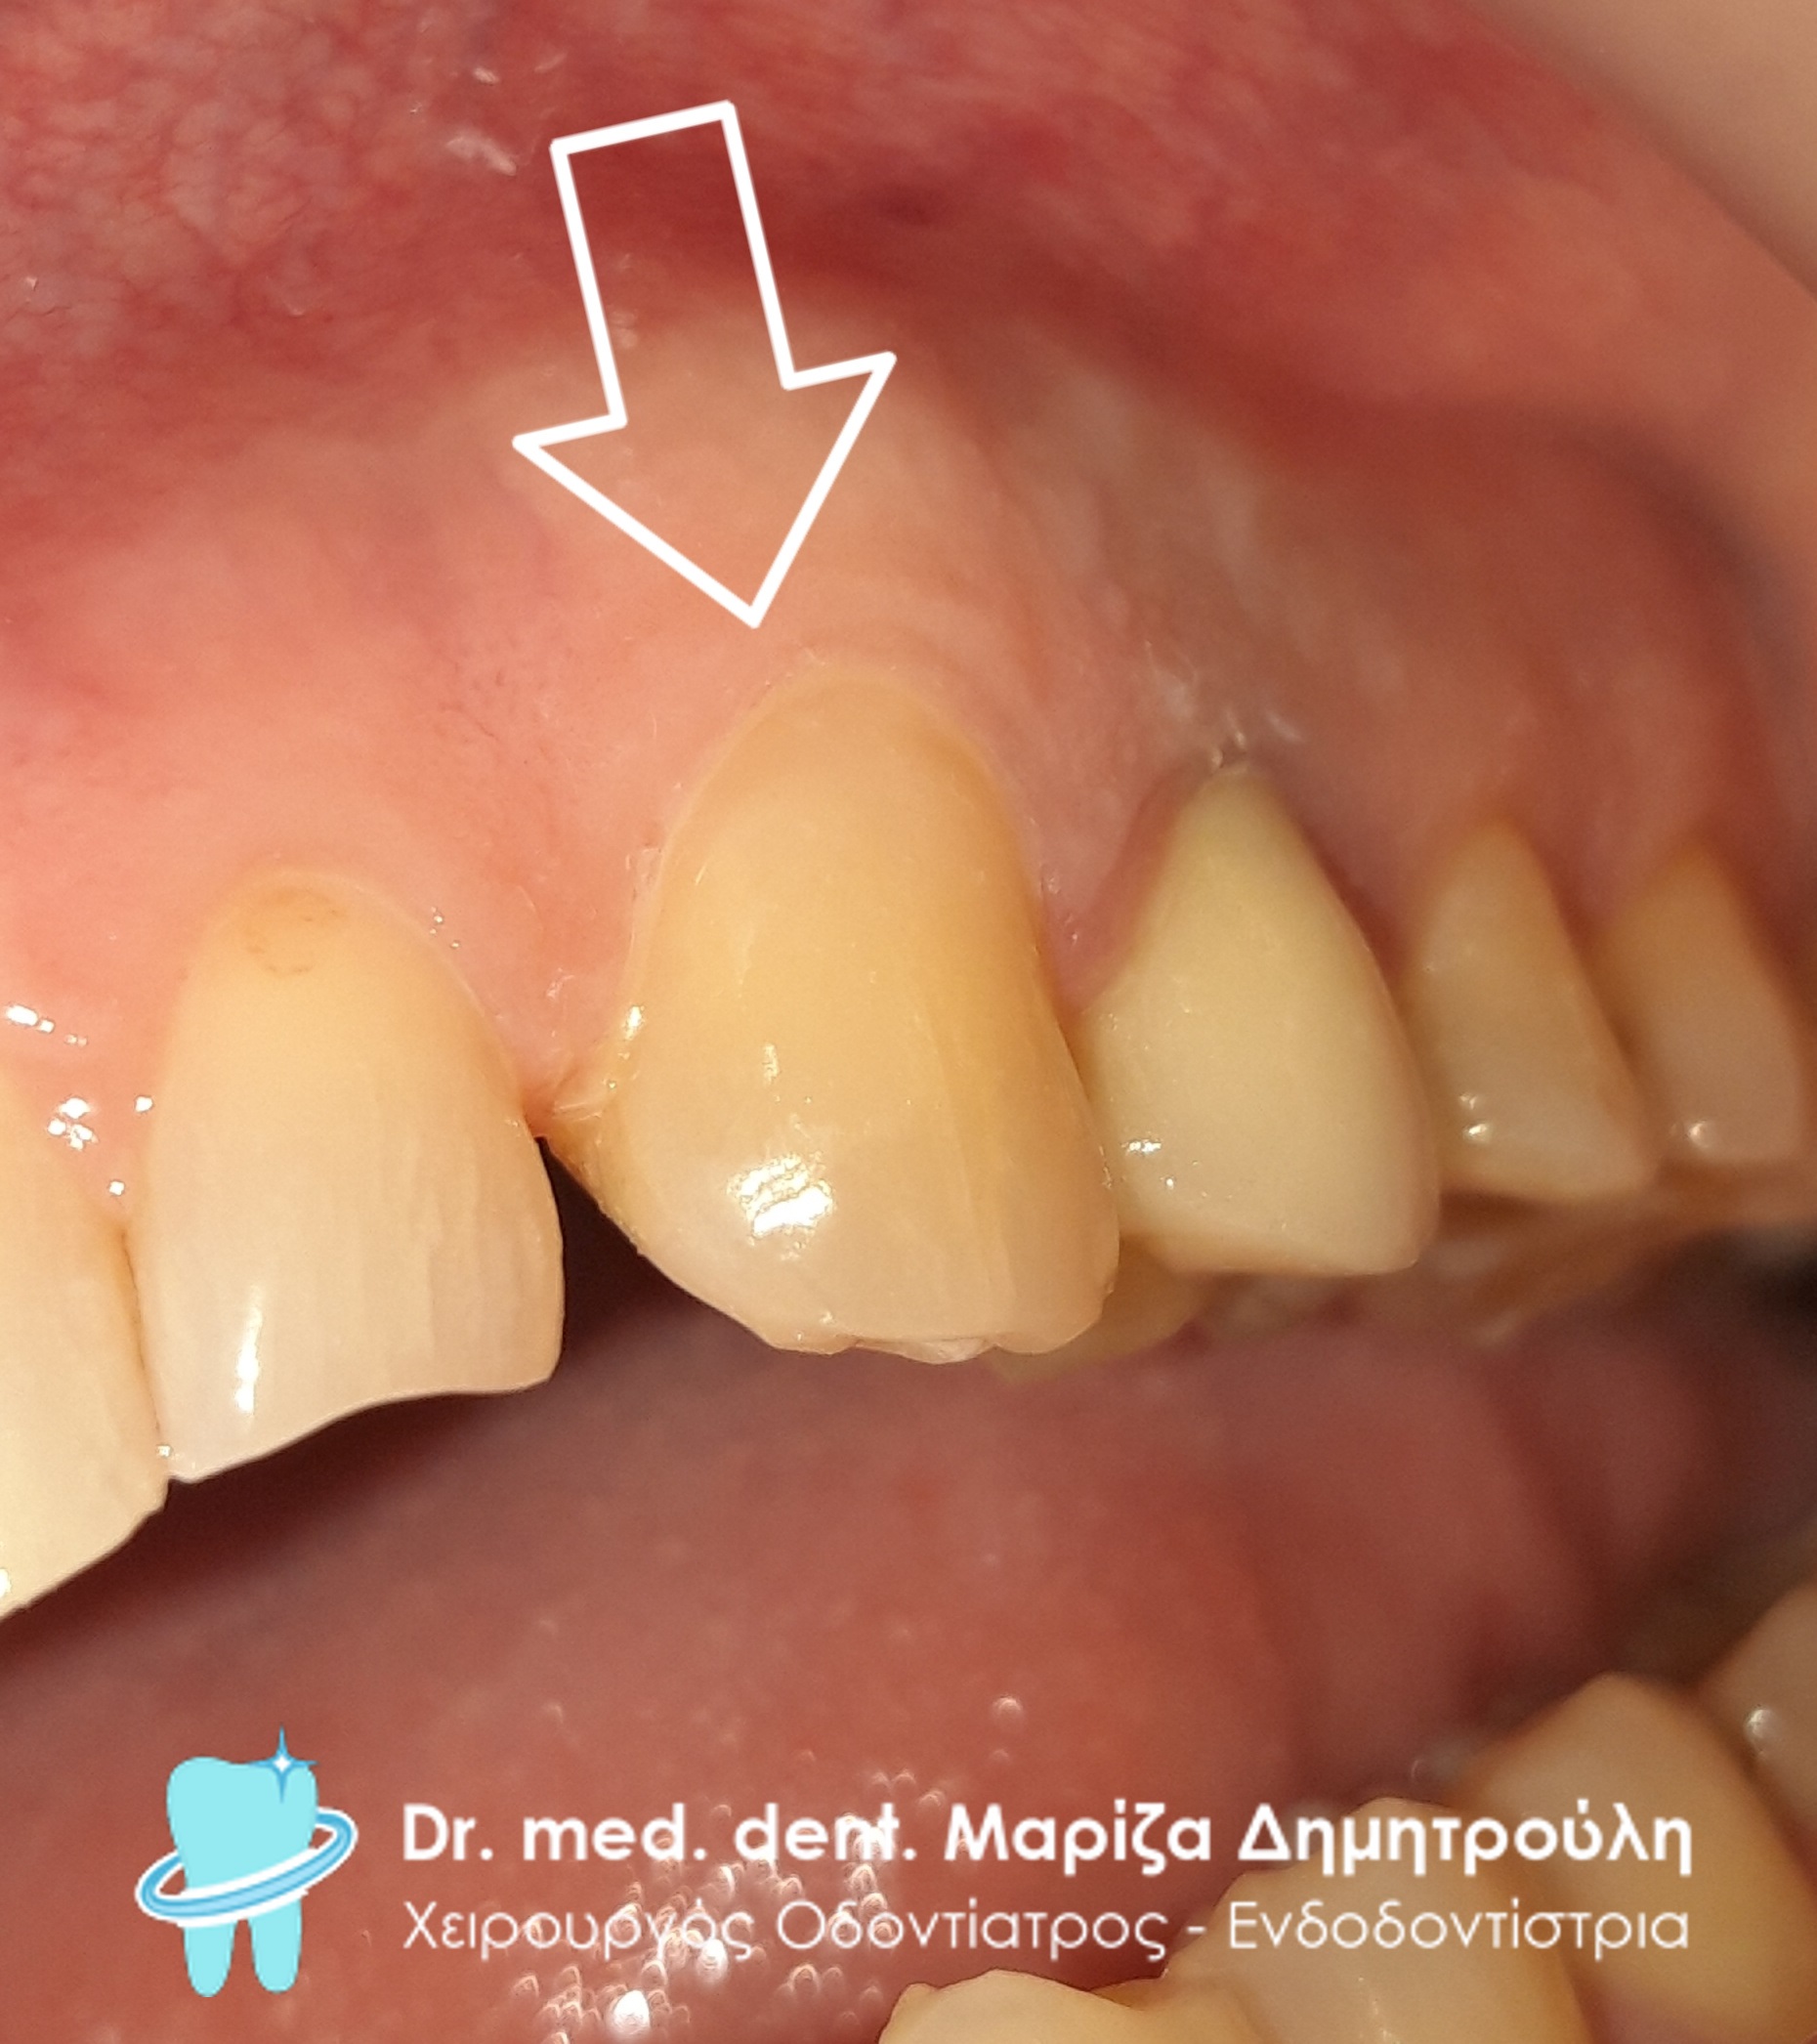

Περιστατικό – Αυχενικά σφραγίσματα δοντιών

Ο ασθενής αναφέρει μία ενόχληση στην αριστερή πλευρά της άνω γνάθου, η οποία δεν είναι μόνιμη αλλά παρουσιάζεται κυρίως κατά τη λήψη ψυχρών ερεθισμάτων, κρύο νερό, παγωτό, κρύα φρούτα κ.α. Η κλινική εξέταση αποκάλυψε μία αυχενική αλλοίωση στον πρώτο προγόμφιο στην αριστερή πλευρά της άνω γνάθου. Μετά τη χορήγηση τοπικής αναισθησίας ακολούθησε η ανασύσταση της αλλοίωσης υπό τη χρήση ελαστικού απομονωτήρα (γαλάζιο ελαστικό) με λευκό σφράγισμα ρητίνης. Ο ασθενής αναφέρει οτι οι ενοχλήσεις έχουν σταματήσει και μπορεί να τρώει πλέον οτι επιθυμεί.

ΠΡΙΝ

META